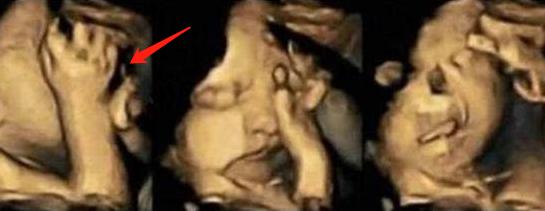

3.“捂鼻胎儿”火了,孕妈做四维彩超遭医生怒斥:真无知

前段时间,30岁的准妈咪小青去医院做四维胎超,当医生看到屏幕画面后,眉头紧锁,她们无法解释胎儿为何会做出如此奇怪的动作。

画面中,胎儿双手捂着鼻子,脸部表情十分痛苦,好似在与某种看不见的东西做抗争。